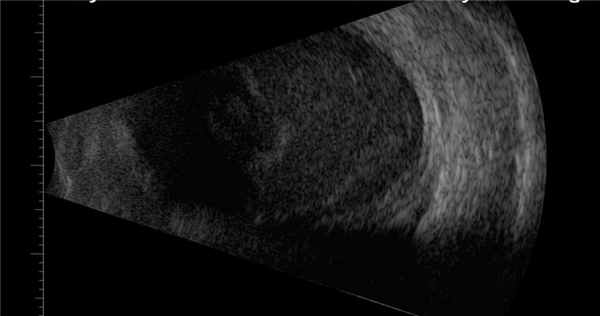

В-сканирование. Экссудат в стекловидном теле.

- УЗИ: уплотнение очагов стекловидного тела, утолщение, приподнятость сетчатой и сосудистой оболочек, наличие фиброзных шварт.